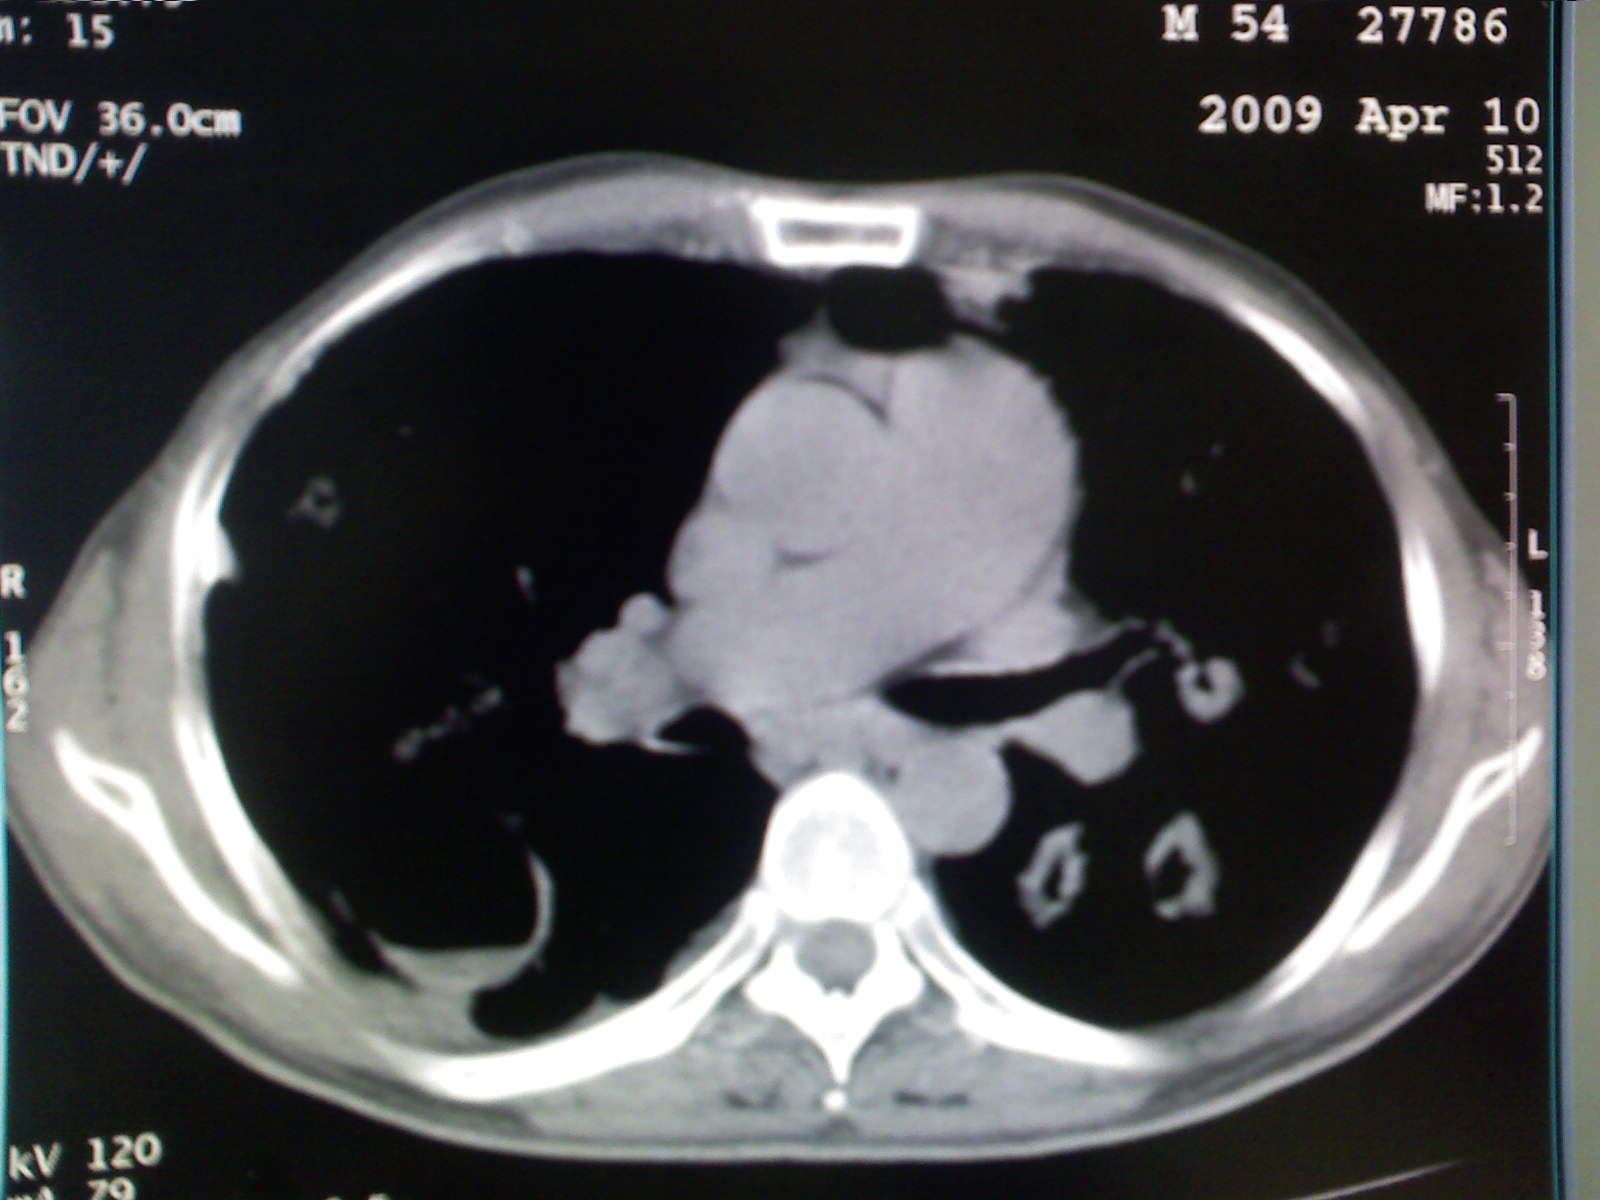

以下是引用卜一在2009-4-11 15:50:00的发言:[br]双肺继发性肺结核伴空洞形成,不排除合并霉菌感染!(病灶呈多形态 多特征 散在分布)。另:合并支气管扩张征伴感染!

以下是引用主力军在2009-4-11 15:55:00的发言:[br]两肺继发性肺结核可能性大。

以下是引用康鹏在2009-4-11 16:30:00的发言:[br]双肺继发性肺结核伴空洞形成合并感染[br]支气管扩张合并感染